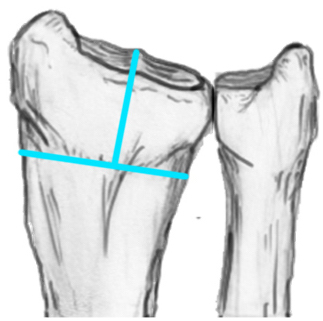

3.   Radial shortening > 5 mm

- leads to ulnocarpal abutment

4.  Radial inclination < 15o

5.  Sagittal tilt

- > 15o dorsal

- > 20o volar

- +/- marked dorsal comminution